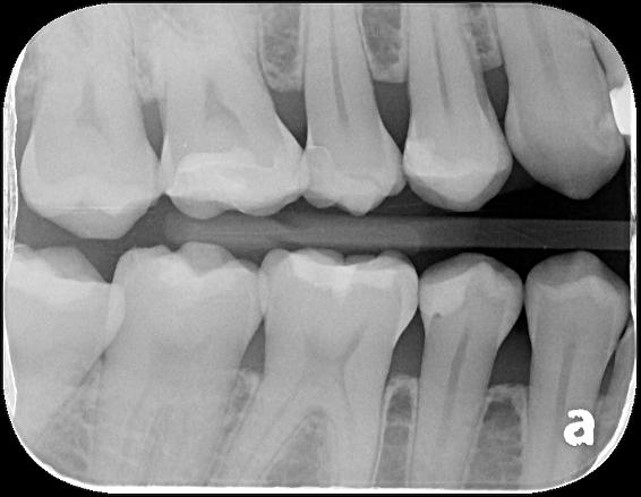

X光可見小臼齒與大臼齒之間有蛀洞

治療後,X光密合度良好